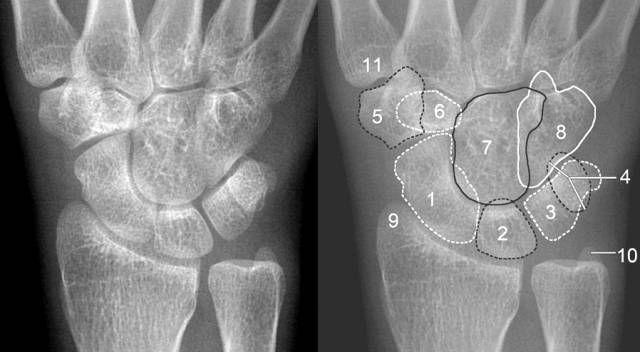

详细的腕关节x线解剖摄影技巧阅片技巧测量

腕关节正位片

腕关节正侧位

腕关节正侧位标准

腕关节正侧位片图片

腕关节正侧位片

腕关节侧位解剖图

腕关节侧位x线图片

腕关节侧位片

腕关节侧位解剖

腕关节侧位解剖图x线

腕关节解剖图x线